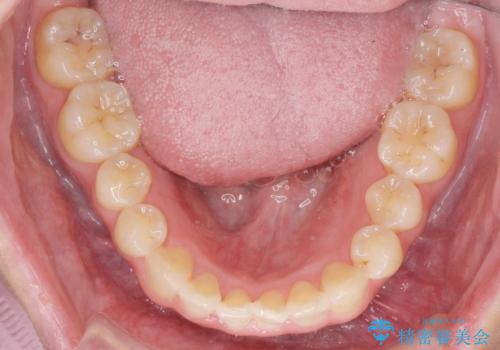

上下の歯のがたつきを改善するマウスピース矯正治療と、下顎に見られる大きな骨隆起を外科的に除去する治療計画を進めていきます。

歯並びが改善したとともに、骨隆起を除去したことで舌をしまうスペースも増え安定した口腔内環境を確立することができました。